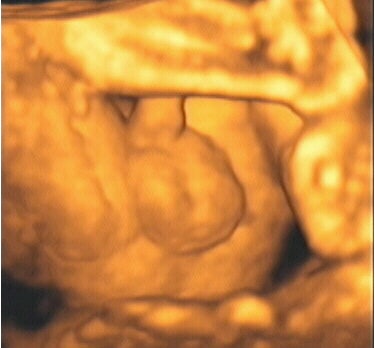

![]() |

| Figure 9, a 3-D ultrasound image of a fetal foot at 28 weeks gestation. Image courtesy of Stefano Ciatti, M.D. |